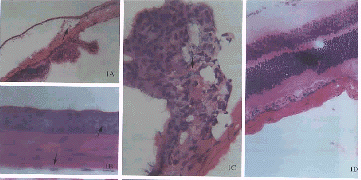

图1 对照组的角膜(A)、虹膜(A,F)、睫状体(A)和视网膜(A,D)。玻璃体腔内注射DOSPER与pGME-7Zf(+)质粒混合液后1周基因转移情况:角膜上皮细胞和内皮细胞(B)、睫状体(C)、虹膜(G)、视网膜节细胞层、光感受器层及色素上皮细胞(E)均可见β-半乳糖苷酶基因的阳性表达 图2 尾静脉注射DOSPER与pGME-7Zf(+)质粒混合液后1周视网膜基因转移情况:脉络膜(a)、视网膜色素上皮细胞(b)、光感受器(c)及节细胞(d)均可见β-半乳糖苷酶基因的阳性表达 Fig.1 Cornea(A),iris(A,F),ciliary body(A) and retina(A,D) in the normal control group.Gene transfer 1week after the injection of DOSPER and pGME-7Zf(+) into the vitreous.Beta-galactosidase expression is seen in the corneal epithelial cells and endothelial cells(B),ciliary body(C),iris(G),retinal ganglion cells,photoreceptors and pigment epithelial cells(E) Fig.2 Gene transfer 1week after the injection of DOSPER and pGME-7Zf(+) into the tail’s vein.Beta-galactosidase expression is seen in the choroid(a),retinal pigment epithelial cells(b),photoreceptors(c) and retinal ganglion cells(d)